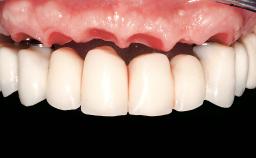

Immediate Loading of Two Implants in the Mandible and Final Restoration with a Bar-Supported RDP

Prosthesis Type RDP

Defining Characteristics Fully edentulous lower jaw to be rehabilitated with an implant-borne removable overdenture

Occlusal Scheme/Issues Balanced